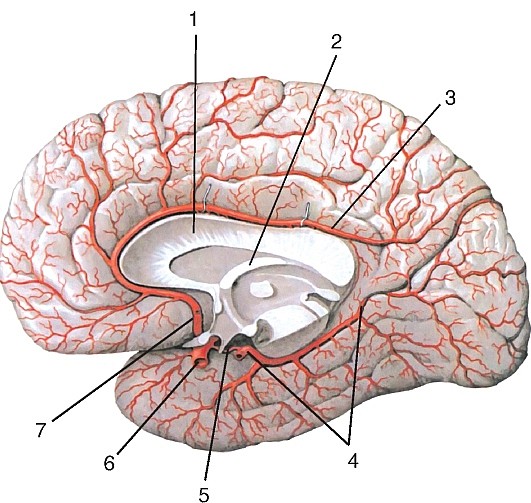

Анатомия: Задняя соединительная артерия мозга